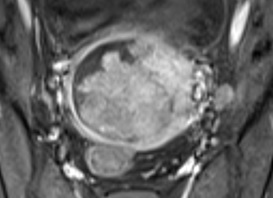

Siêu âm bé sau sinh tại bệnh viện Nhi đồng 1 ghi nhận ở vùng sau phúc mạc bên trái có một khối không đồng nhất kích thước: 53x81x75mm với hình ảnh vòm sọ, cột sống, mô mở và xương dài bên trong và đẩy thận trái xuống hố chậu. Siêu âm chẩn đoán: Thai trong thai.

Hình 5: Siêu âm em bé sau sinh, ở sau phúc mạc và trên thận có một khối không đồng nhất với hình ảnh vòm sọ (dấu sao) và cột sống (mũi tên)

MRI được chỉ định trong những trường hợp siêu âm không rõ ràng, giúp thu hẹp chẩn đoán phân biệt. MRI an toàn đối với thai, giúp đánh giá bản chất của các thành phần bên trong khối, đánh giá chính xác vị trí của khối thai bên trong thai chủ, đánh giá tốt trong trường hợp thai phụ béo phì. Nhược điểm của MRI không sẵn có, đắt tiền, thời gian chụp lâu, và hạn chế ở người phụ nữ không thể nằm lâu, thai cử động nhiều, thai phụ sợ nhốt kín.